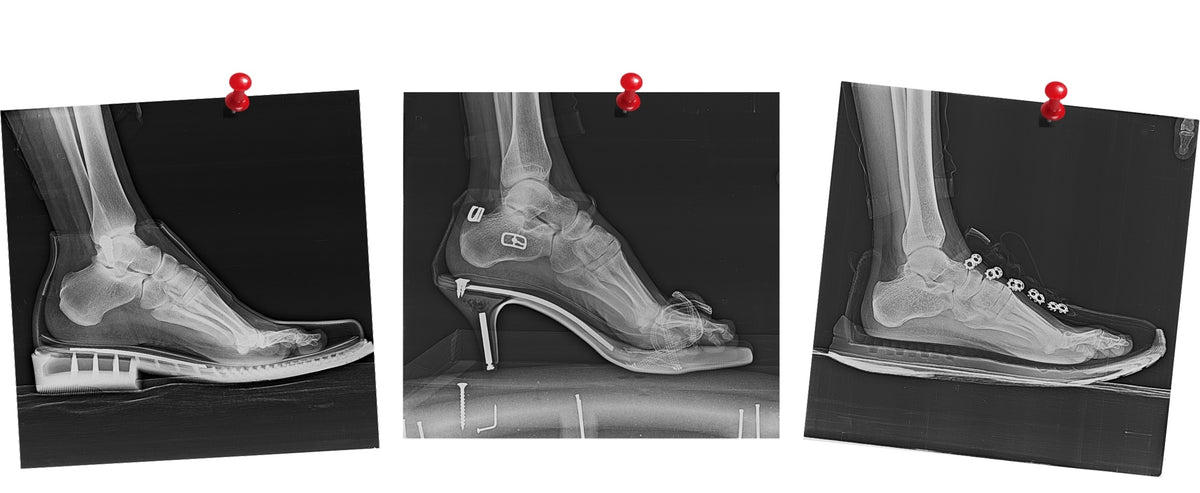

Harmful environment for your feet

Regular shoes with a narrow toe box, heel elevation, and thick, stiff soles create an artificial environment for your feet.

They restrict the natural movement of your feet and reduce sensory feedback from the ground. This artificial environment negatively impacts your entire body

Heel Elevation vs. Zero-Drop Sole

Understanding the Impact Zero-Drop Design on Foot Health